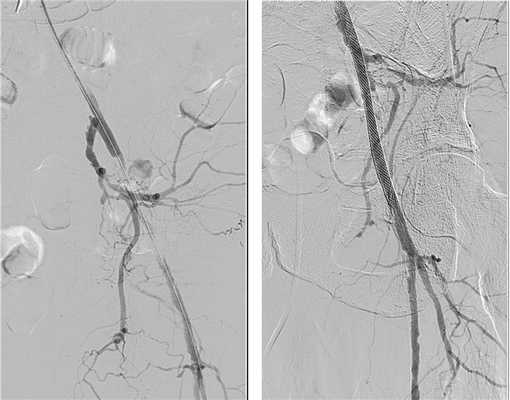

Также часто выполняется наложение бедренно-дистального шунта с одномоментным стентированием вышележащих сегментов (бедренной и/или подвздошных артерий). Данный вид вмешательств используется достаточно давно. Так, в 2001 году Schneider с соавт. впервые описали технику выполнения одномоментной ангиопластики сужений ПБА в сочетании с наложением бедренно-берцового шунта у больных с критической ишемией нижних конечностей [12]. В госпитальном периоде ни у одного из 12 пациентов не было отмечено окклюзии шунта, ампутаций также удалось избежать. Через 2 года частота первичной проходимости артерий составила 76%. Пример гибридного стентирования левой ОПА в сочетании с наложением бедренно-берцового шунта представлен на рис. 1.